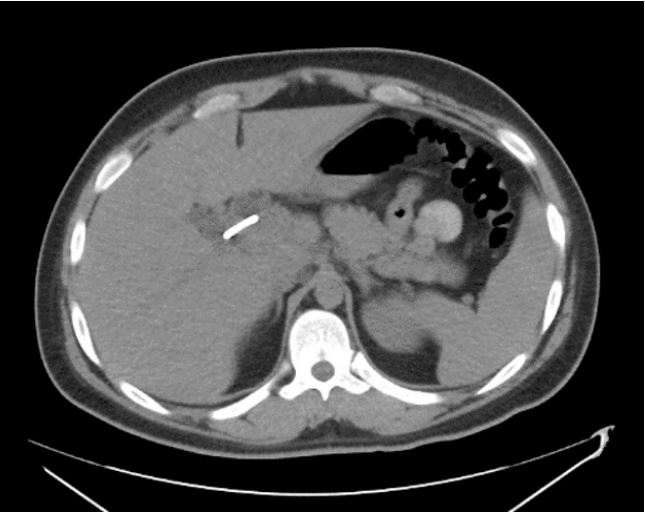

The patient was brought in for an emergent repeat ERCP. During the procedure, it was noted that the distal tip of the biliary stent had invaginated into the lateral wall of the duodenum or possibly extraluminal in the retroperitoneal space (Figures 1-3). Patient was then admitted, and general surgery was consulted. He was taken to surgery where it was confirmed that the single pigtail biliary stent had eroded through the duodenum. Procedures performed during surgery included a bile duct exploration, cholecystectomy, choleoducoduodemostomy, and duodenal repair. Patient was treated with intravenous Zosyn while hospitalized. Post operatively the patient responded well with routine post operative care, antibiotics, and fluids.

Figure 1: ERCP image of Biliary stent coming out of ampulla and invaginating into the opposite duodenal wall.

Figure 3: Computed tomography impression: Stent seen in the dilated common hepatic and common bile ducts to the duodenum. The common bile duct (CBD) is normal size. Common hepatic duct and intrahepatic biliary duct are dilated. Pancreatic duct is not dilated.